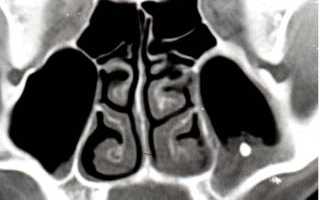

Врачи отмечают, что наличие инородного тела в гайморовой пазухе может привести к серьезным осложнениям. Чаще всего такие случаи возникают после травм, хирургических вмешательств или при попадании посторонних предметов, например, во время занятий спортом. Симптомы могут варьироваться от легкого дискомфорта до выраженной боли, отечности и затрудненного дыхания. Важно, что своевременная диагностика и лечение играют ключевую роль в предотвращении инфекций и других осложнений. Врачи рекомендуют при подозрении на инородное тело обращаться за медицинской помощью, так как самостоятельные попытки удаления могут усугубить ситуацию. Современные методы визуализации, такие как КТ, позволяют точно определить местоположение и характер инородного объекта, что значительно облегчает дальнейшее лечение.

Если вы заметили указанные симптомы или не можете справиться с хроническим гайморитом, рекомендуется пройти полное диагностическое обследование. Этот процесс включает несколько этапов:

- при необходимости – компьютерная томография.